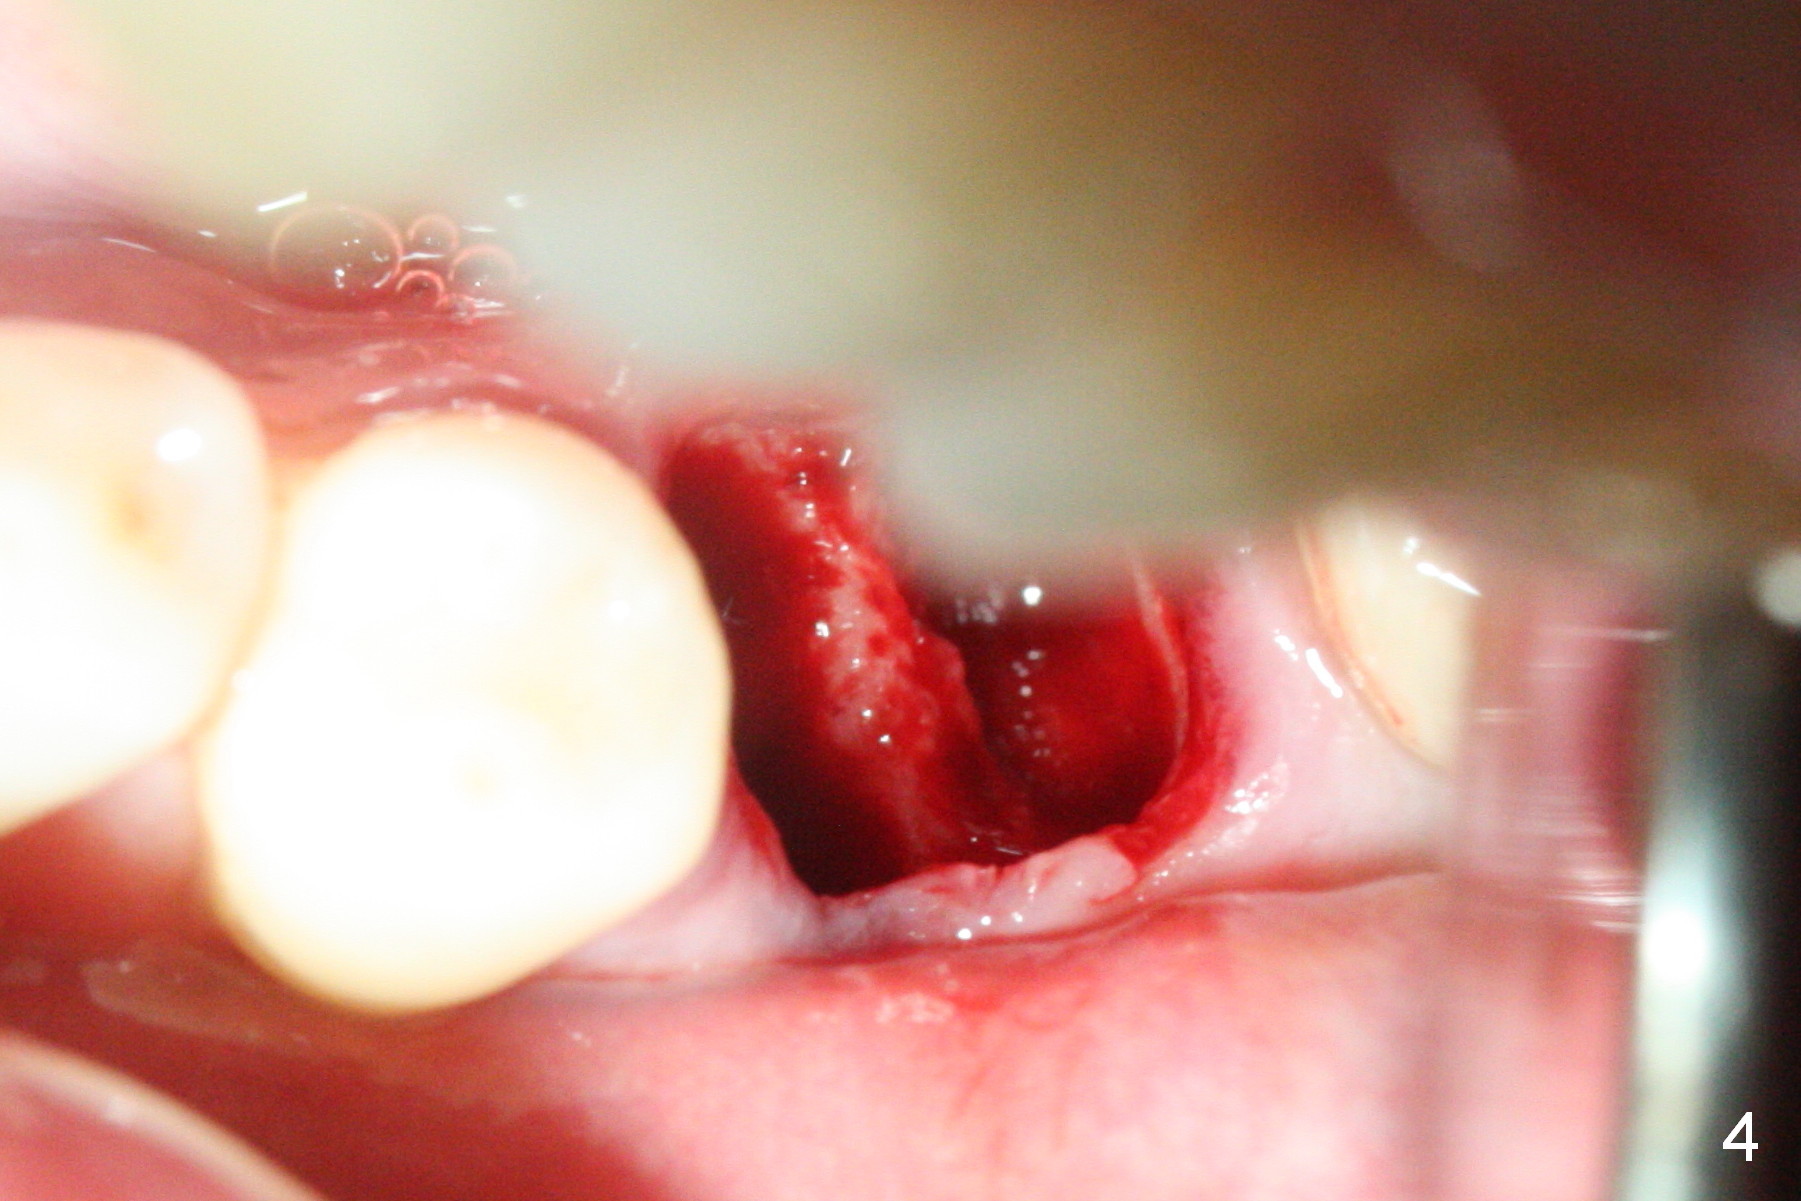

The tooth #19 is easy to get loose, but it cannot be luxated. After sectioning and extraction (Clindamycin), the septum is found to be thin (Fig.4). A surgical fissure bur is used to initiate osteotomy, followed by 1.6 mm pilot drill. It is difficult to use Marking bur (wobbling over the basically pointed septum). It is impossible to use 4.3 mm Magic Drill (MD, one drill system), since it jumps. The smallest MD has to be used (2.8 mm). When the next drill (3.3 mm) is being used for 13 mm with stopper (Fig.5), the patient experiences transient pain. The depth is suggested from the design in Fig.2. The thin septum appears not to be a reliable landmark. When block anesthesia is administered, the initial depth should be shortened. The drill appears to be close to the Inferior Alveolar Canal (Fig.5). Then the depth changes to 11 mm with the following drills (3.8 and 4.3). The mesial and distal walls of the septum are gradually perforated. A 5x9 mm dummy implant is placed only after using 4.8 mm drill (Fig.6). The implant appears to be short. When a longer implant is placed (5x11 mm), it does not easily enter the osteotomy, either sliding into the mesial or distal socket with the implant separating from the implant driver. It appears that a premount implant is appropriate in this situation. When the 5x11 mm implant is finally seated with stability, it is 6 mm apical to the gingival margin. The longest cuff of IBS abutment is 4 mm. A longer implant is needed (Fig.7, 5x13 mm). Placement is not easy as mentioned above. Insertion torque is <20 Ncm when the patient experience a little discomfort. A 6.5x4(4) mm pair abutment is placed (A), apparently proper for restoration. Allograft is placed (Fig.8 *) prior to immediate provisional. The patient complains of bad smell from the site 24 days postop. When the provisional is removed, the abutment is found to be mobile. When the latter is removed with local anesthesia, bone graft granules are attached to the socket above the lightly mobile implant (Fig.9). In fact the latter appears to be stable after a few turns by finger. A healing screw is placed; the socket is closed with collagen plug and 4-0 Chromic gut sutures (Fig.10). It appears that a larger implant should have been used to achieve higher torque. Two months later (3 months postop), the coronal end of the implant is partially exposed. A 5x4 mm healing abutment is placed. It appears that the implant is stable. The implant appears to have osteointegrated 4 months postop (Fig.11). Impression is taken.